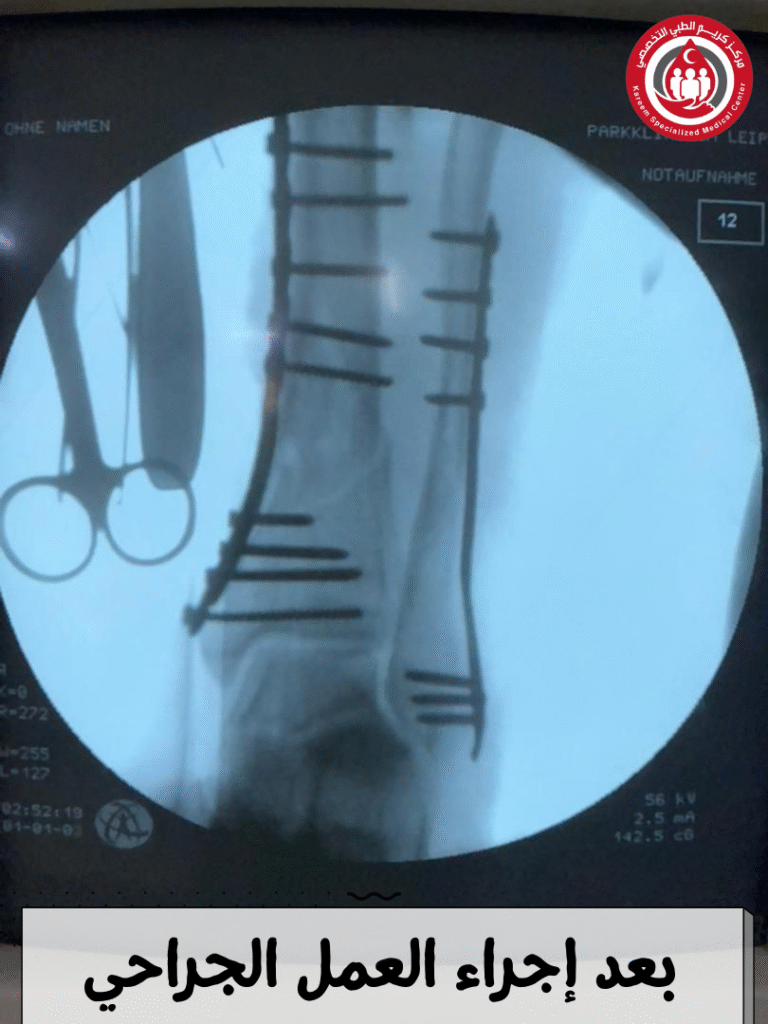

وبعد مراجعة نتائج الصورة والتقييم السريرِي، تبيّن أن طبيعة الكسور تتطلب ردًا تشريحيًا دقيقًا وتثبيتًا داخليًا لضمان إعادة المحور الطبيعي للقدم والحفاظ على الوظيفة المستقبلية للمفصل. تم إدخال المريض إلى غرفة العمليات حيث أُجري له تثبيت داخلي للكسور باستخدام صفائح تشريحية وبراغٍ مقفلة (Locking Screws) لتحقيق الثبات الميكانيكي المطلوب وتعزيز الالتئام العظمي بالشكل الأمثل.

تم التأكد خلال الجراحة من دقة الردّ واستقرار المفصل عبر الفحص المباشر والصور الشعاعية داخل العملية، ثم جرى تثبيت القدم بواسطة جبس بلاستيكي (Fiberglass Cast) لمدة تقارب 45 يومًا لحماية منطقة الكسر ومنع أي حركة قد تؤثر على نتائج التثبيت.